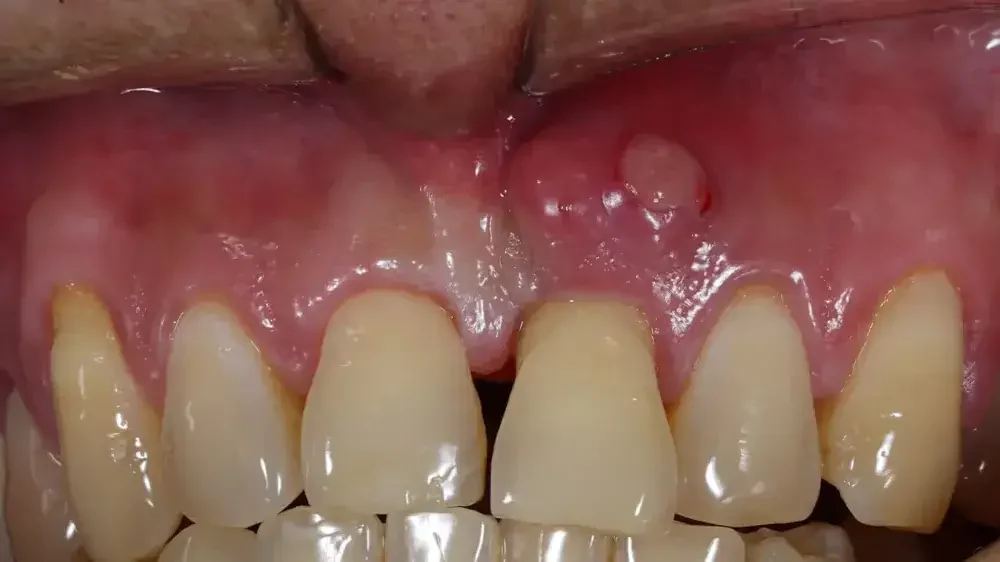

Selain nyeri, pembengkakan pada area gusi yang terinfeksi juga merupakan gejala yang umum pada abses gusi. Gusi di sekitar gigi yang terinfeksi akan membengkak dan terasa lembut saat disentuh.

Biasanya, pembengkakan ini disertai dengan perubahan warna gusi yang menjadi lebih merah atau bahkan merah gelap, menandakan adanya peradangan.

Gejala lain yang sering muncul pada abses gusi adalah keluarnya nanah dari area gusi yang terinfeksi. Nanah ini merupakan hasil dari infeksi bakteri dan dapat terlihat sebagai cairan berwarna kuning atau putih yang keluar dari lubang kecil di gusi atau gigi.